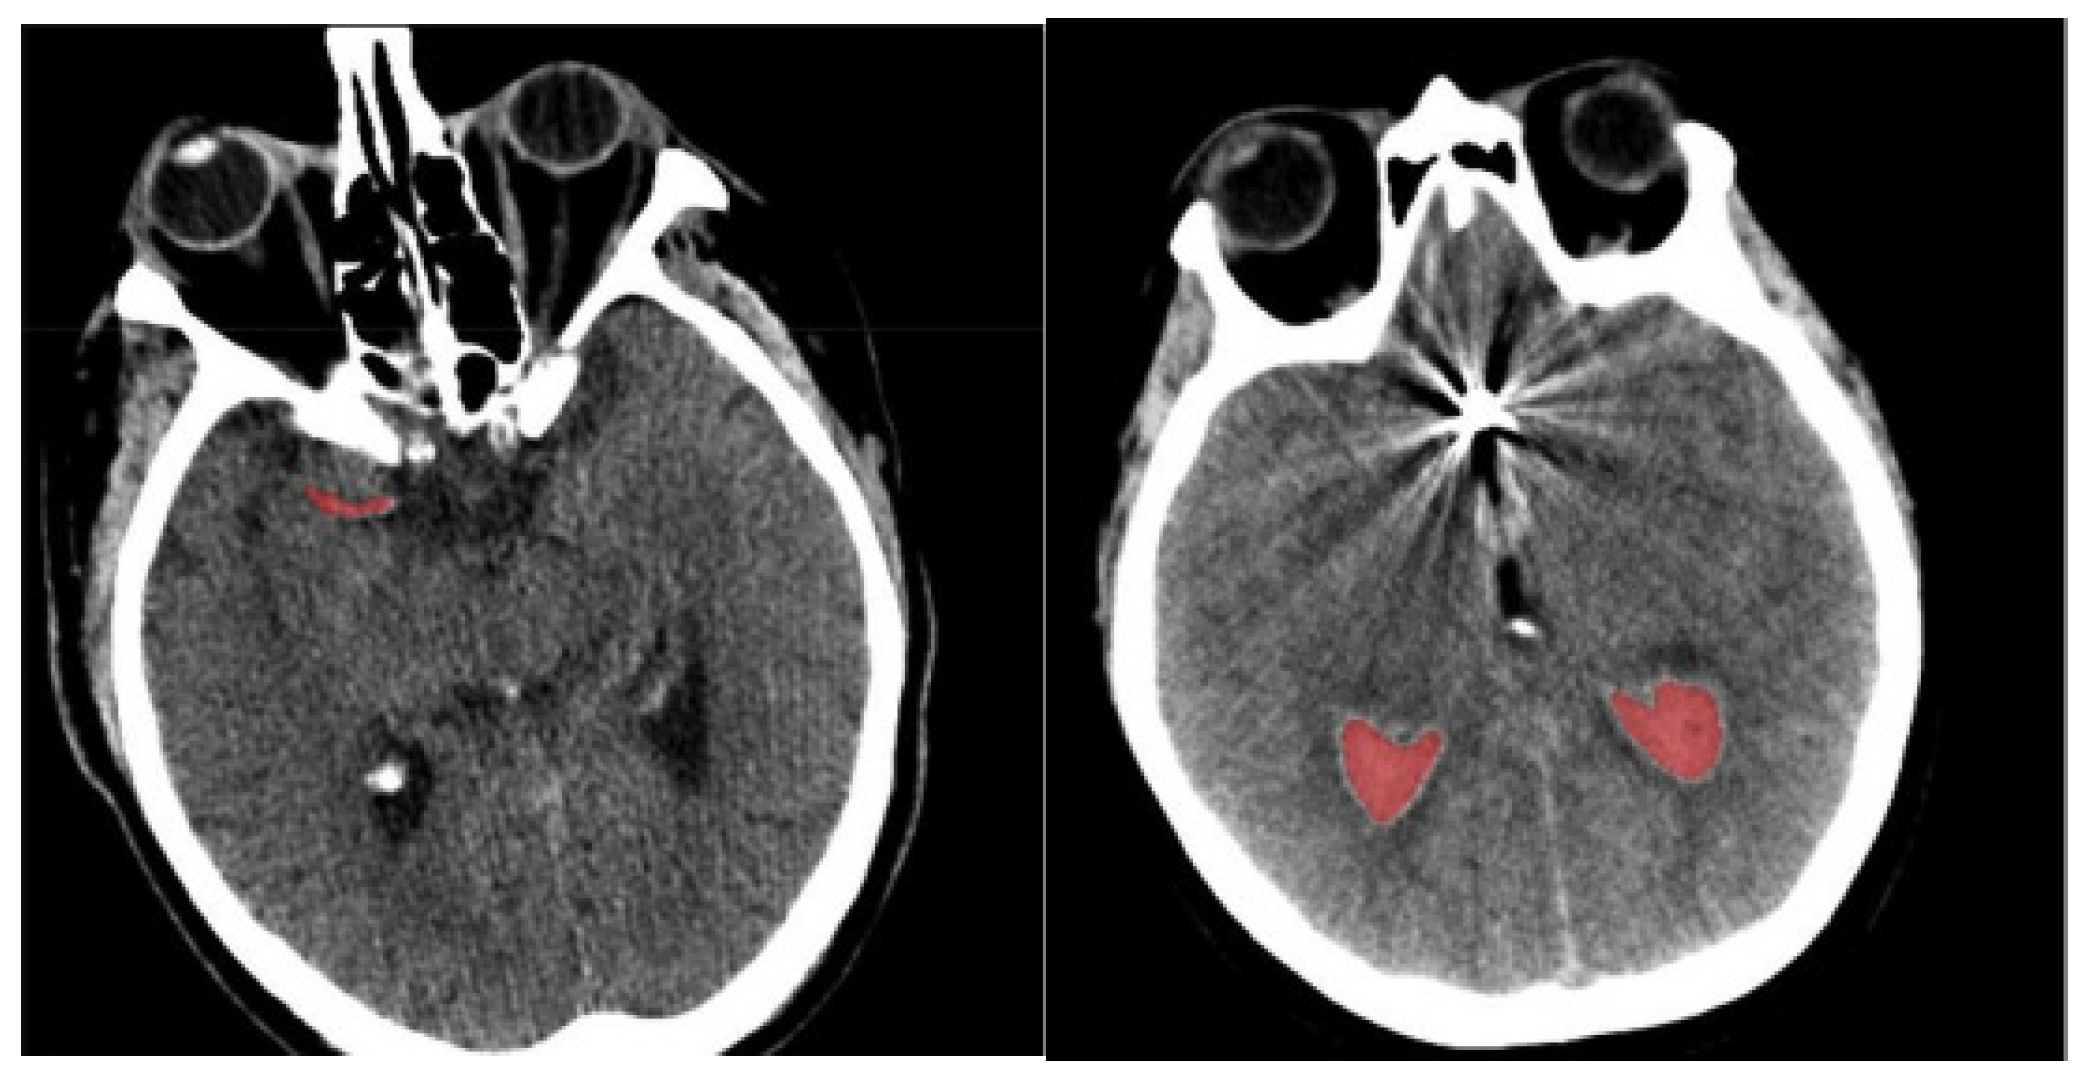

- Finally, determine the differences in orientation and intensity of the pixels and using Equations (3) and (4). The sample-segmented images are graphically presented in Figure 3, where the red area denotes the segmented portions.